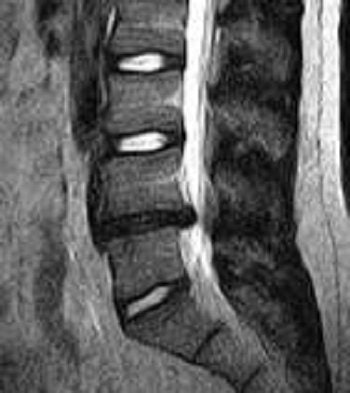

| Above, midsagittal T2-weighted MRI showed increase in stenosis at the L4 level by 2.0 mm with ventral thecal sac compression with axial loading (below). All images courtesy of Dr. Gerald Anzalone. |